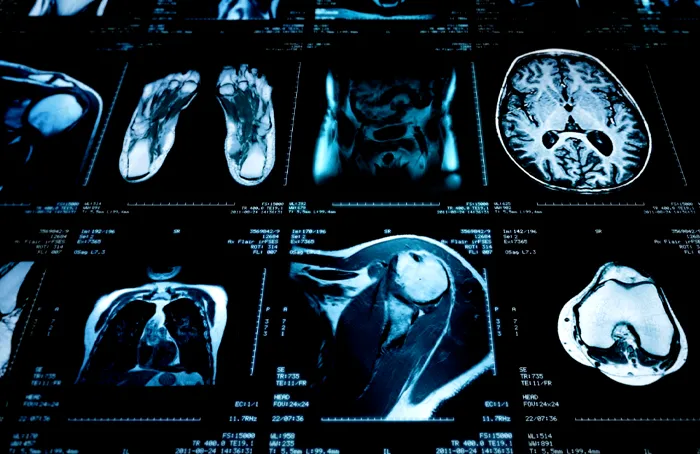

Prendersi cura della propria salute significa prevenire in modo attivo, valutando tutte le possibilità diagnostiche disponibili, come la Risonanza Magnetica Total Body (WB-MRI), una delle tecnologie di imaging attualmente più avanzate.

La Risonanza Magnetica consente di rilevare precocemente patologie in fase asintomatica e ottenere una valutazione completa dell’intero organismo con un singolo esame, senza l’utilizzo di radiazioni ionizzanti.

La ricerca scientifica ha dimostrato che la WB-MRI rappresenta uno strumento di screening oncologico altamente efficace. Un panel multidisciplinare di esperti, coordinati dall’Istituto Europeo di Oncologia, ha sviluppato ONCO-RADS un protocollo standardizzato ampiamente validato che garantisce la massima accuratezza nella diagnosi precoce dei tumori.